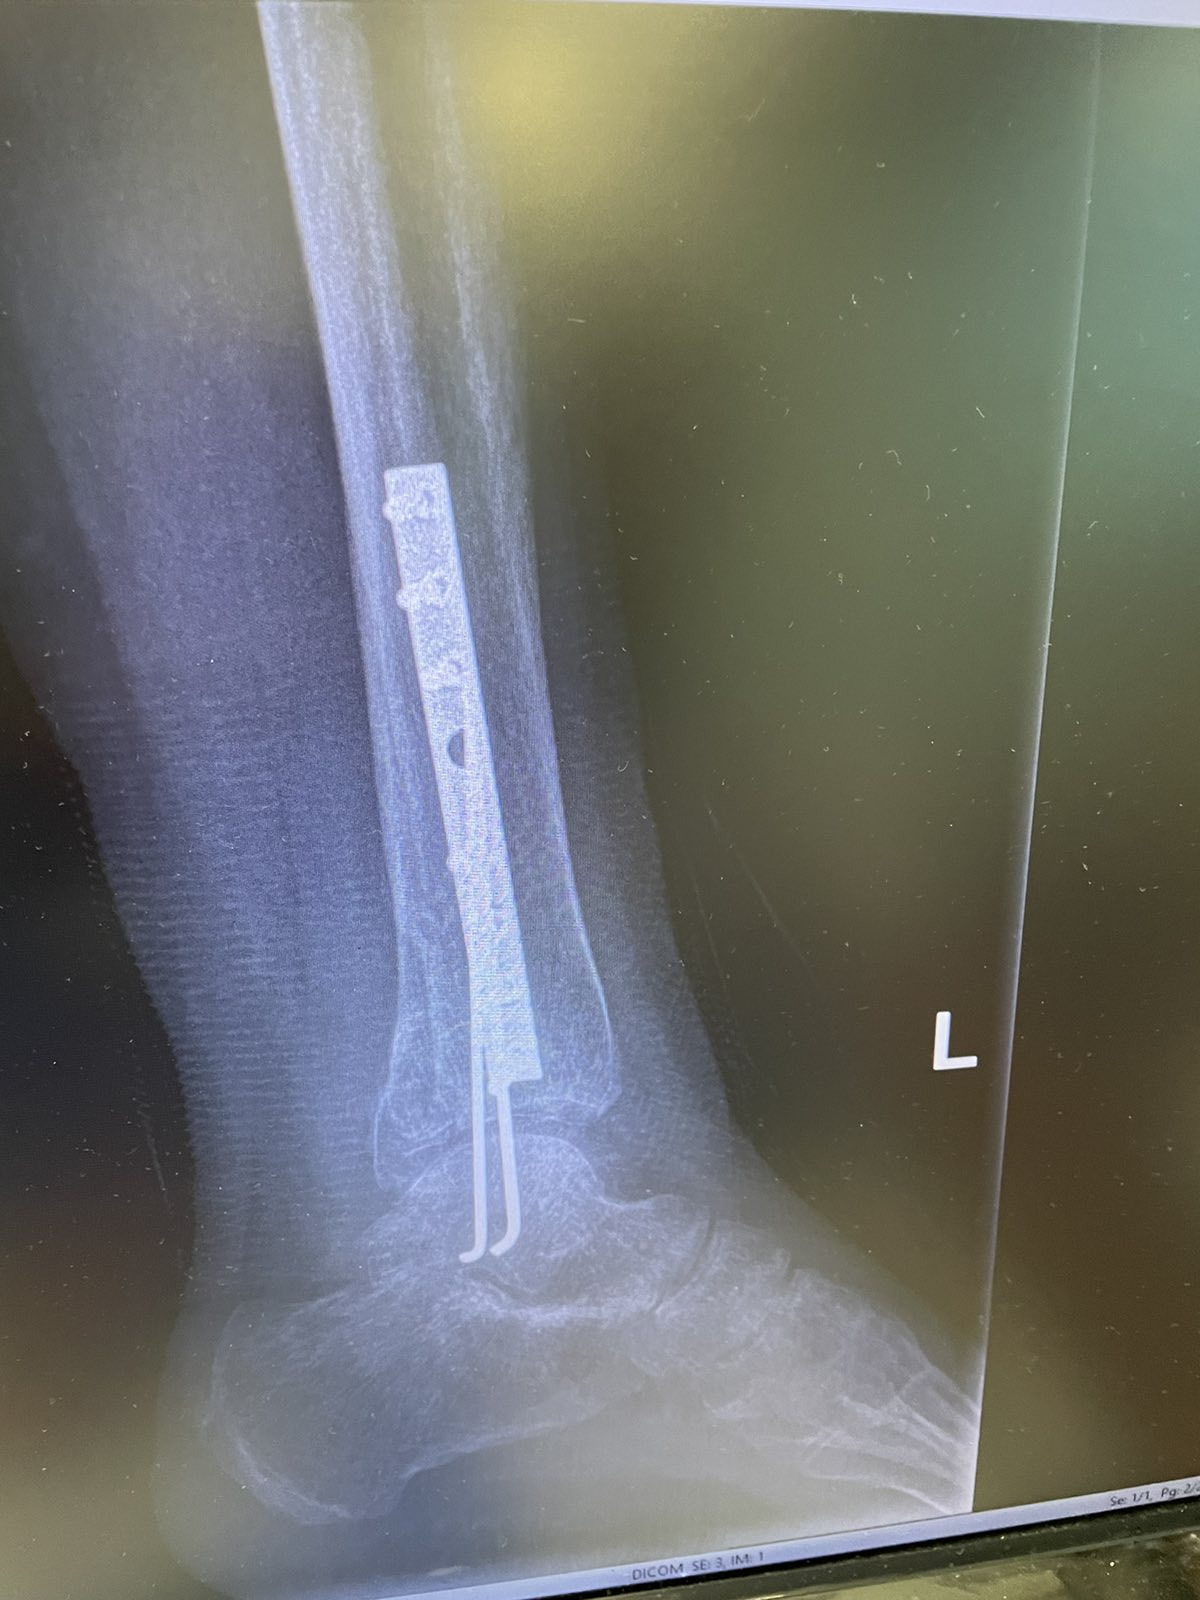

Mišljenja sam da je količina osteofiksacionog materijala pozamašna. Jedino tako je Vaš prelom mogao biti saniran. Moguće je malo popraviti stanje mekog tkiva ( ligamenata, mišića i tetiva

) mobilizacijom skočnog zgloba, a za pun obim pokreta mislim da će tr dobiti tek kada taj materijal bude izvadjen.

U poruci koju ste mi poslali, dostavili ste i RTG snimak vašeg preloma iz koga se može zaključiti da su prelomi masivni te da je ortoped morao da ugradi veliki broj ostefiksacionog materijala ( šrafova ).

Oni su tu sa ciljem da vam ograniče pokrete tako da je oticanje noge, umor i hramanje normalna pojava.

Mišljenja sam da će do kompletnog oporavka doći kada isti budu odstranjeni obično se to dešava 12 – 18 meseci posle operacije. Do tada morate biti uporni sa veżbama za jačanje, istezanje i propriocepciju mišića stopala i skočnog zgloba.